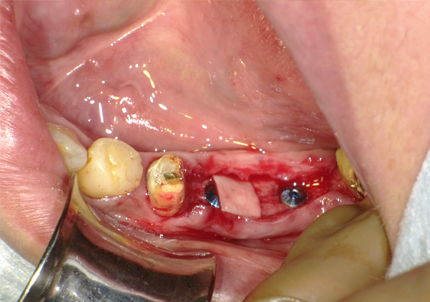

5.インプラント埋入(2021年6月)

※ 初期固定35N/cm確認する